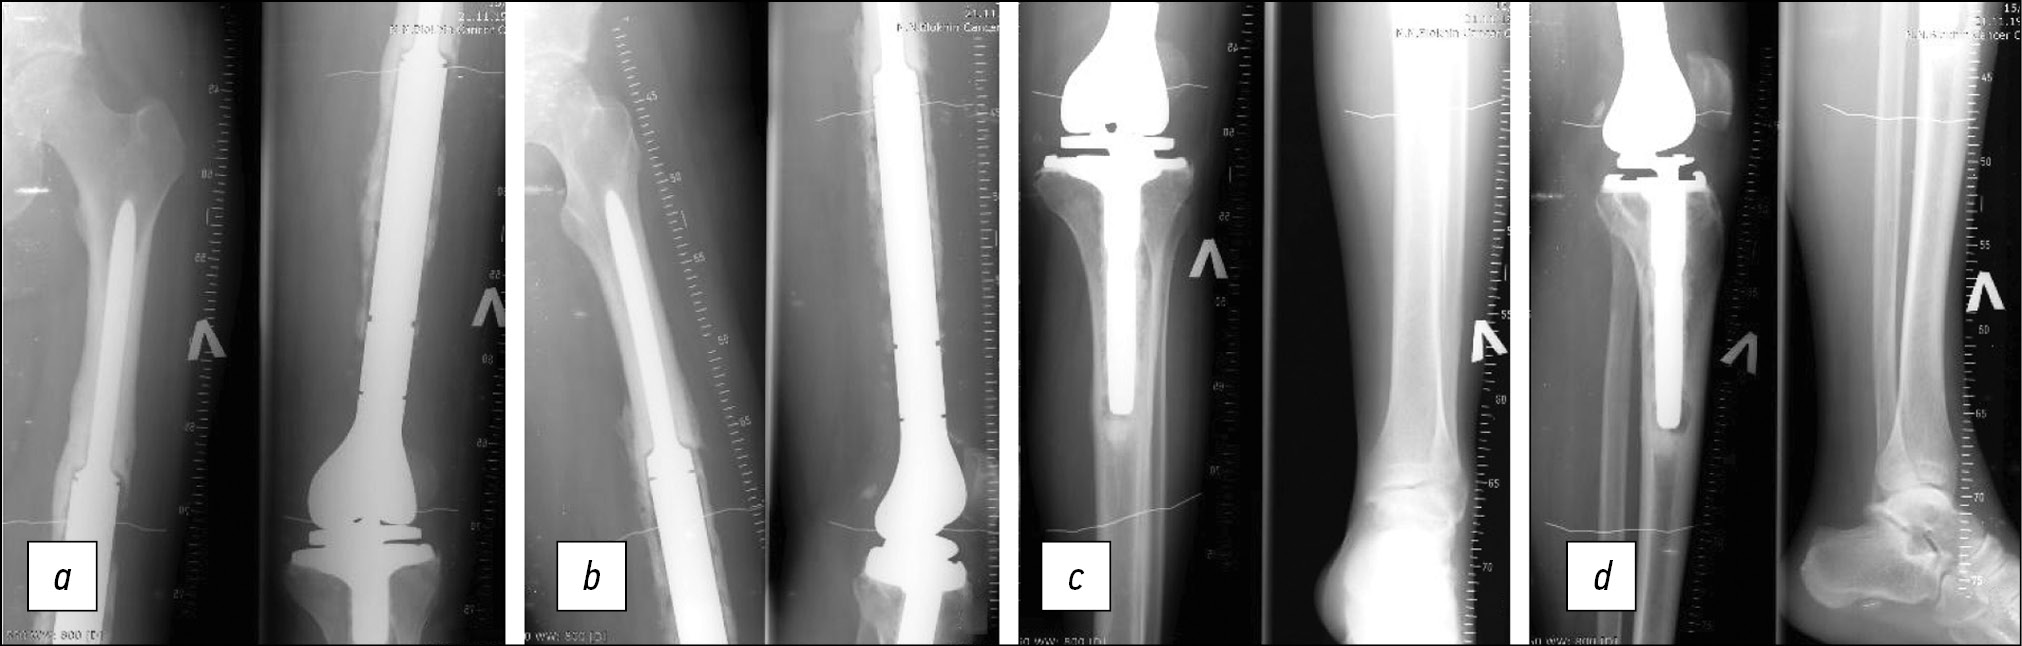

On June 15, 2022, left knee joint re-endoprosthesis (stage II) was performed. A modular cemented endoprosthesis by Stryker was installed (Fig. 9).

Fig. 9. X-ray after stage II knee revision endoprosthetics (2022): a — femoral stem of the endoprosthesis, frontal projection; b — femoral stem of the endoprosthesis, lateral projection; c — tibial pedicle of the endoprosthesis, frontal projection; d — tibial pedicle of the endoprosthesis, lateral projection.